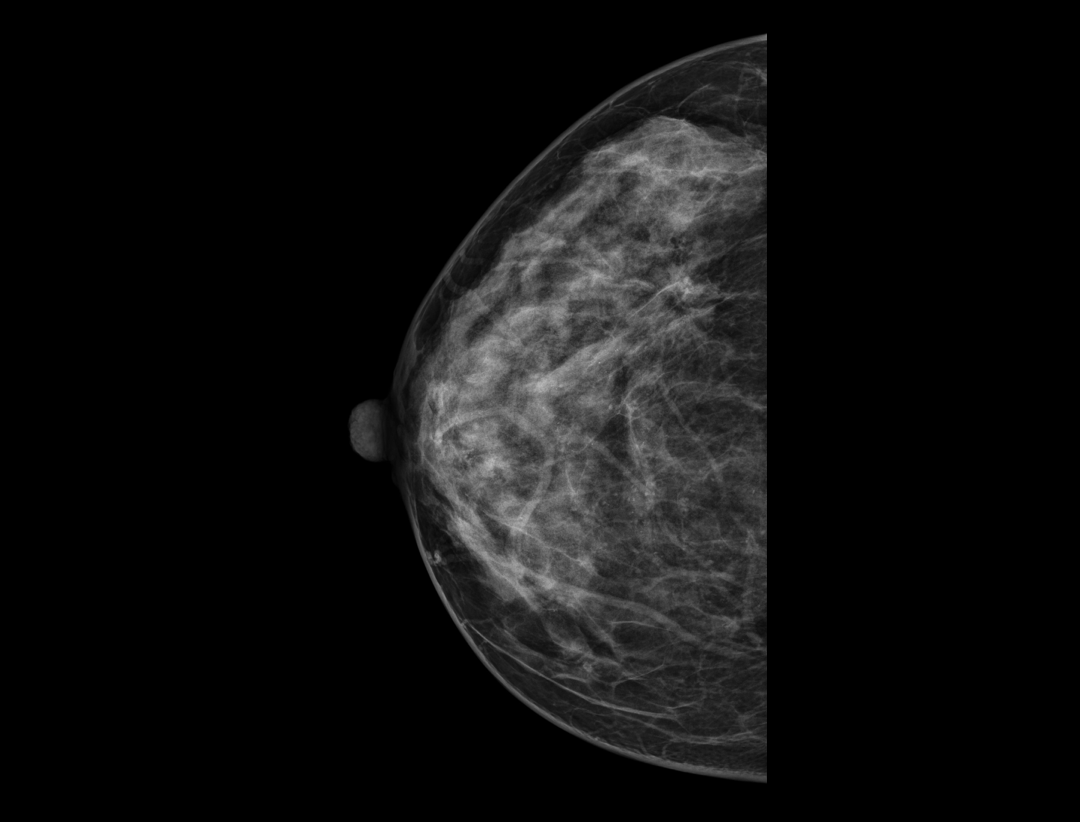

Adaptacyjne dostosowanie grubości warstwy tomosyntezy zapewnia szczegółowe obrazowanie przestrzenne zmian chorobowych i skupisk mikrozwapnień.

Hybrydowe protokoły wyświetlania pozwalają na synchroniczne wyświetlanie obrazów 2D i warstw tomosyntezy w celu łatwego porównania. Dostępne są zarówno pogrubione warstwy (slabs), jak i widok płaszczyzny.